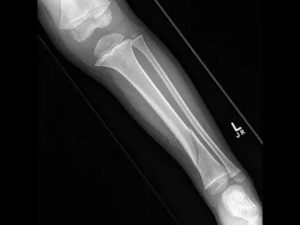

Представляем снимок несмещенного перелома большеберцовой кости.

Переломы со смещением

В 80-90% случаев наблюдают смещенные переломы берцовой кости. Смещение развивается по причине посттравматического сокращения мускулатуры. Сокращение мышц в участке перелома является защитной реакцией организма, направленной на предотвращение повреждения нервов и сосудов.

Вторая причина смещения фрагментов кости – воздействие на нее веса тела. Часто наблюдаются случаи, когда стабильный перелом малоберцовой кости под воздействием массы тела переходил в нестабильный (смещенный).

Костные участки могут смещаться вдоль оси кости или поперек нее. Смещение вдоль оси является менее благоприятным, поскольку риск травмирования сосудисто-нервных образований в такой ситуации стабильно высок. Для осевого смещения отломков характерно проникновение в участки между костными отломками мягкотканевых образований, что отягощает терапию таких переломов.

Переломы со значительным смещением тяжело поддаются консервативным способам терапии, чаще требуют оперативного вмешательства.

Рентген-снимок перелома малой берцовой кости, смещенного по оси.